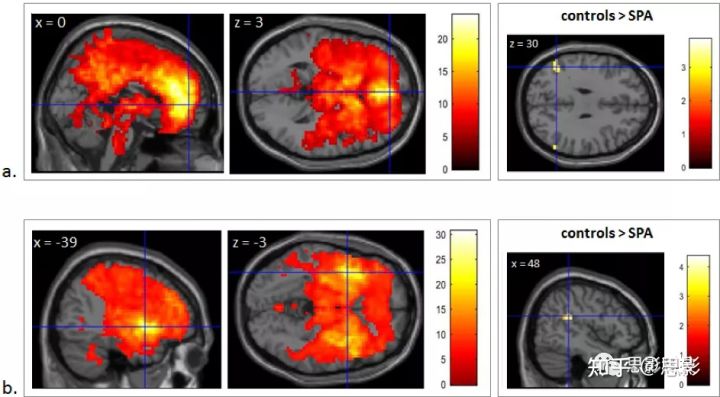

图3:在所有研究参与者中,SPAI和GMV之间呈现负相关的区域。

显示的全脑回归分析结果与年龄、性别、TIV和BDI共变,未校正,k> 80体素 (VBM)和k>5体素(ALFF) p < 0.001。颜色条表示t值。

- 3.5 功能连接性分析

在单样本t检验中,右侧ACC的FC在皮质中线区域的差异显著,包括:后扣带回皮层和楔前叶,以及双侧丘脑、纹状体、岛叶、外侧前额叶、眶额和颞顶叶区域。左侧前脑岛的FC(功能连接)也有类似的变化。在这两种网络中,与对照组相比,SPA患者的下顶叶(IPL)区域的FC均较低。特别是对于右侧ACC的FC,左上缘回、角回和右侧角回连接性较低。右侧岛叶前部FC,右侧边缘上回可见较低FC(立体定位坐标、Z-scores和图参见补充数据)(图4)。

a. 左图:右侧ACC功能连通性。为了便于说明,该图显示了一个样本的矢状和轴向切片,结果来源于回归了年龄、性别和FD的单样本t检验分析, 经FWE校正后p < 0.05。

右图:SPA和对照组之间的显著FC差异,结果来源于回归了年龄、性别和FD的ANCOVA分析, p < 0.005,未校正,k > 30体素。颜色条表示t值。

b. 左图:左前岛叶的功能连接性。为了便于说明,该图显示了一个样本的矢状和轴向切片,结果来源于回归了年龄、性别和FD的单样本t检验分析, 经FWE校正后p < 0.05。

右图:SPA和对照组之间的显著FC差异,结果来源于回归了年龄、性别和FD的ANCOVA分析, p < 0.005,未校正身高,k > 30体素。颜色条表示t值。